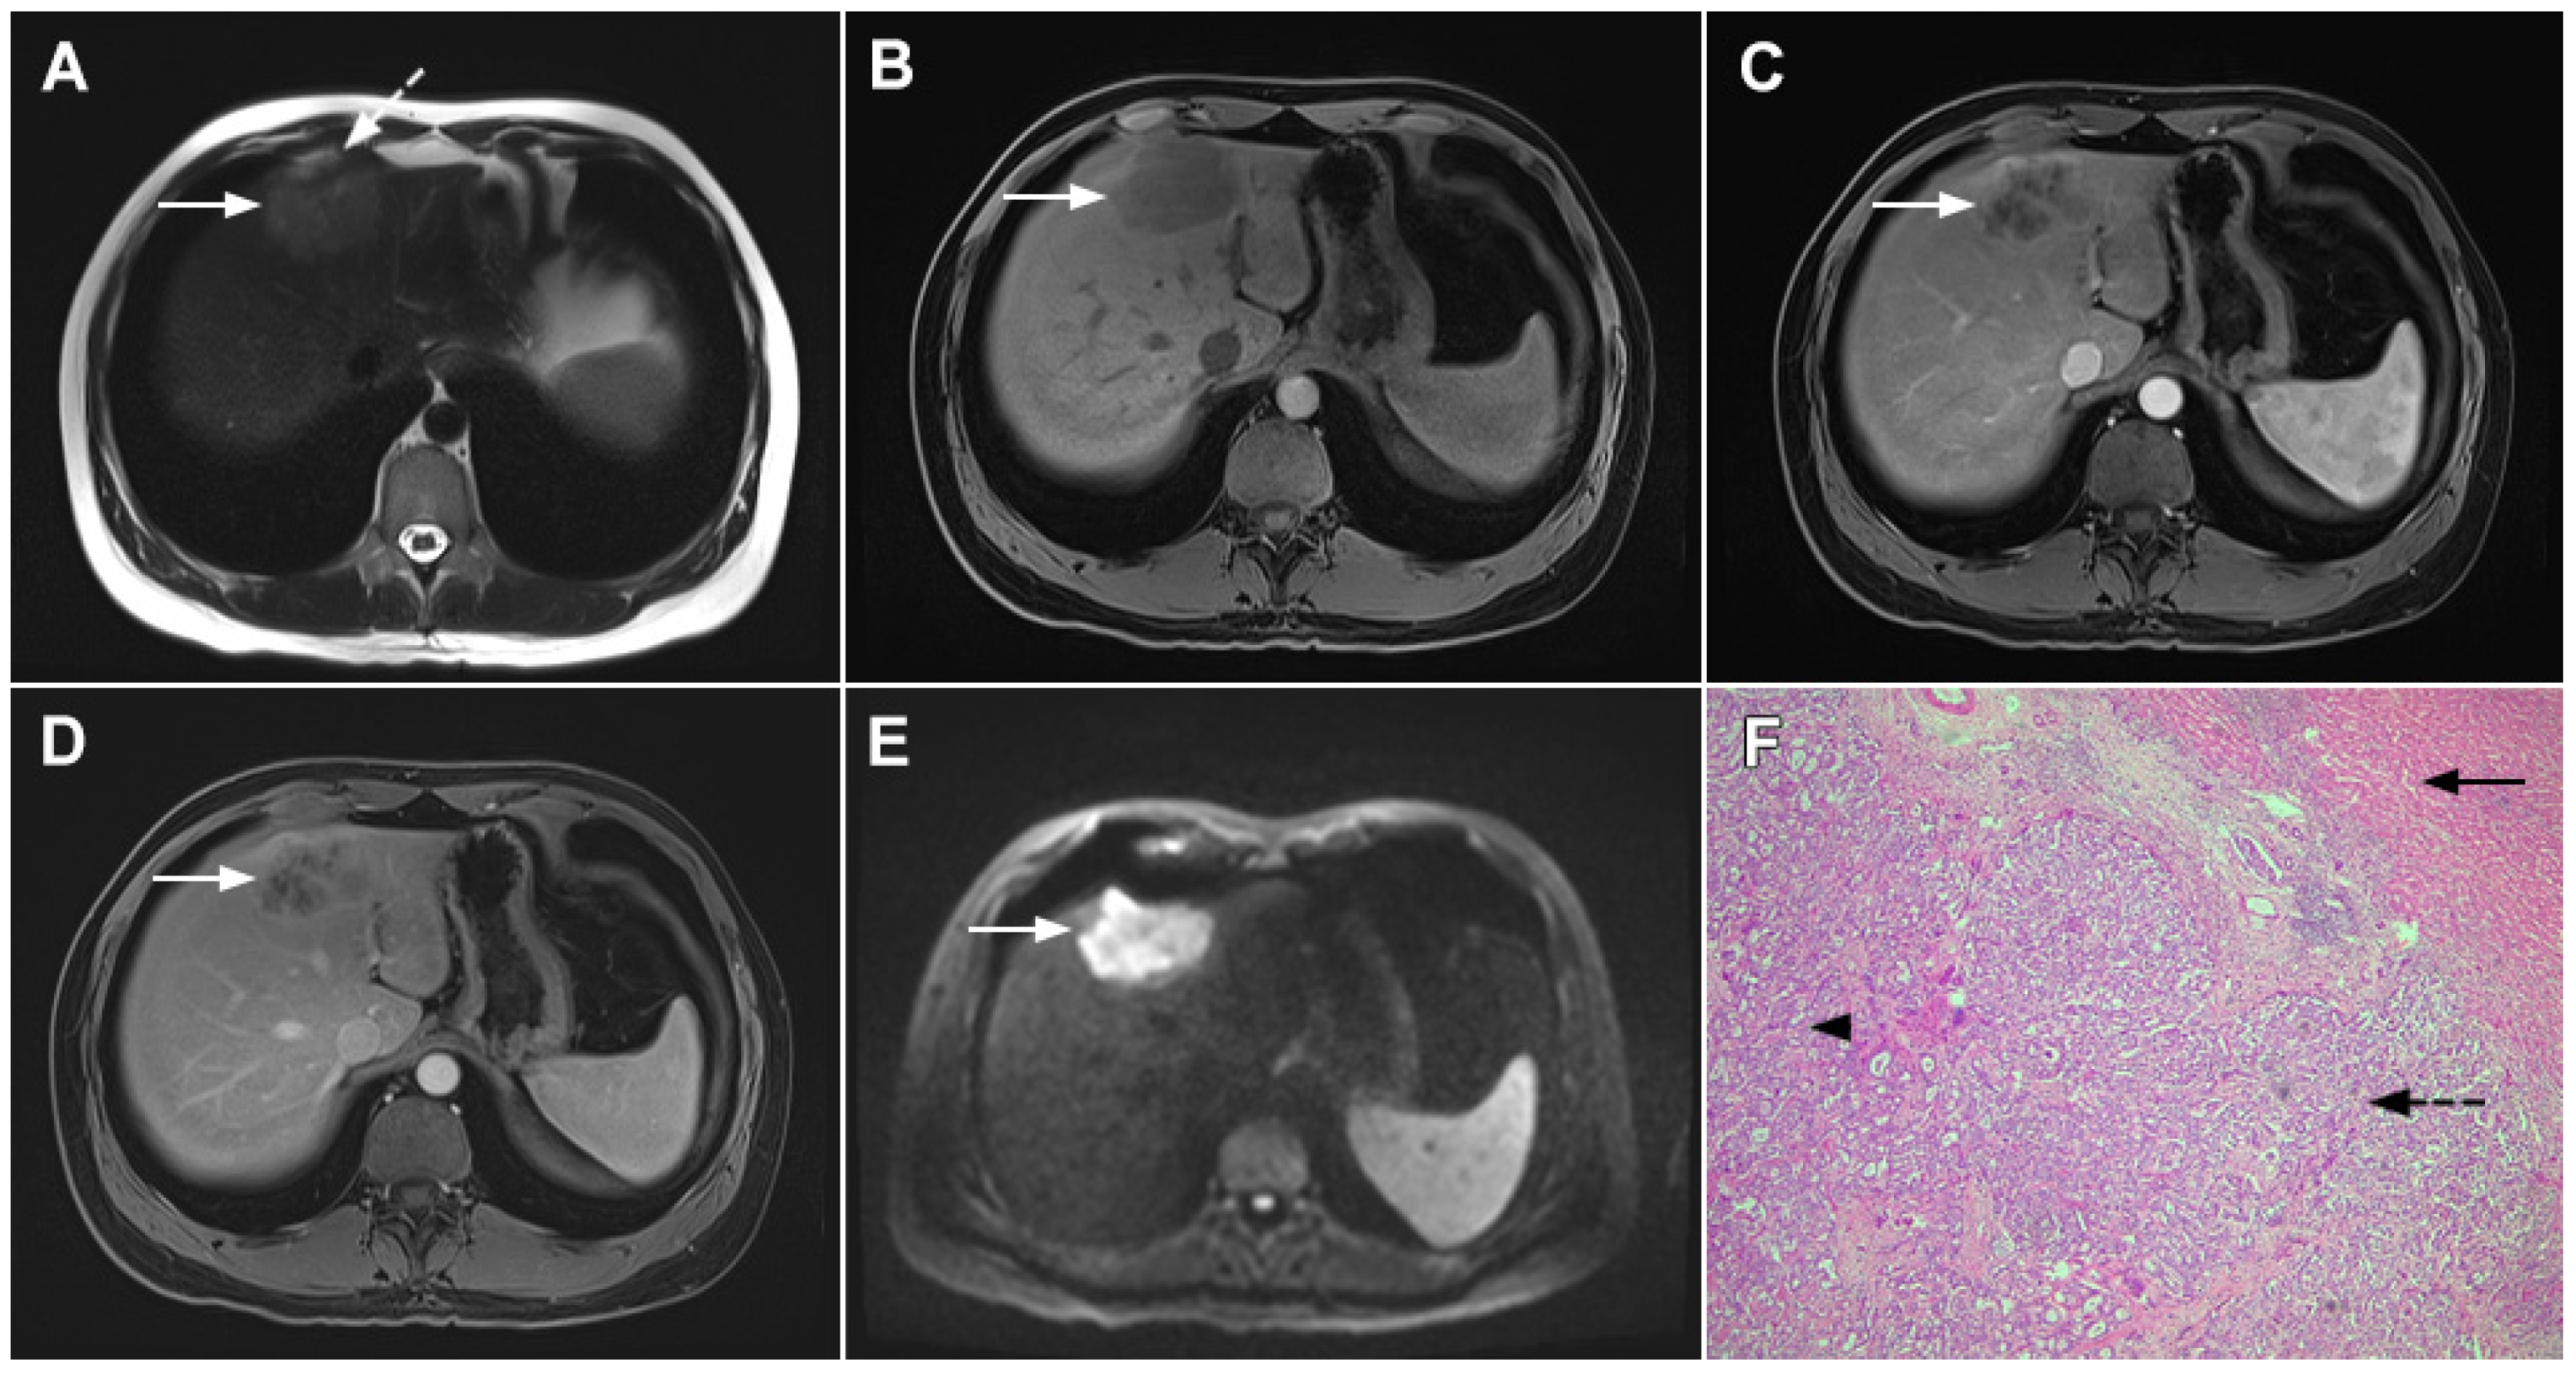

Scirrhous HCC is a rare variant of HCC characterized by rich intralesional fibrotic stroma with incidence of 4.6% among all HCC cases [76]. Scirrhous HCCs are usually seen in MRI scans as lobulated T1-weighted hypointense lesions with a heterogeneous signal intensity on T2-weighted images [77]. With regard to its vascular behavior, Kim et al. showed that the most common enhancement pattern was a peripheral rim-like enhancement in the arterial phase with a progressive central enhancement in the portal–venous and equilibrium phase, which is indistinguishable from mICC (Figure 17) [78]. Moreover, in previous studies washout was seen in only 19% of scirrhous HCC, in comparison to 99.7% of typical HCCs [78]. In addition, similarly to mICC, scirrhous HCC may also cause capsular retraction if it is subcapsular [79]. With regard to the targetoid appearance in the DWI and hepatobiliary phase, both mICC and scirhous HCC can display these imaging features [80]. Therefore, differentiation between scirrhous HCC and mICC represents a real diagnostic challenge, since both lesions have rich fibrous stroma, similar postcontrast behavior, and occur in cirrhotic livers [77]. Concerning different treatment strategies for these tumors, preoperative distinction is very important. In this context, the ancillary feature favoring the diagnosis of mICC include peripheral biliary dilatation, while the presence of a capsule suggests scirrhous HCC [77]. Moreover, the presence of part of the tumor enhancing avidly in the arterial phase favors the diagnosis of scirrhous HCC over mICC [80]. Additionally, Choi SY et al. have shown that mICC more frequently showed T2-weighted central brightness due to the presence of internal necrosis or mucin accumulation [79]. Nevertheless, if the lesion with imaging features of both scirrhous HCC and mICC is seen in the setting of chronic liver disease, according to the Liver Imaging Reporting and Data System (LI-RADS) it is characterized as LI-RADS M and further biopsy is required [81].

Figure 17.

Scirrhous hepatocellular carcinoma in a 68-year-old woman. The axial T2-weighted image (A) shows a moderately hyperintense subcapsular-located lesion in liver segments VI and V (arrow). Note also the capsular retraction. The tumor (arrow) is hypointense in the plain T1-weighted FS image (B), with ring enhancement in the arterial phase (C) and slight progressive central enhancement in the portal venous (D) and delayed phases (E). Hematoxylin and eosin (H&E) staining showed hepatocellular carcinoma (arrow) and normal liver parenchyma adjacent to the tumor (dashed arrow); original magnification ×40 (F).

Poorly Differentiated HCC

The absence of a typical HCC vascular enhancement pattern may be observed in poorly differentiated, large, and sarcomatous HCC [81]. Namely, in sarcomatous HCC neovascularization is not sufficient to supply the rapidly growing sarcomatous component, leading to central ischemia. Similarly, in poorly differentiated HCCs the presence of central no enhancing areas is a frequent finding due to a decrease in the arterial blood supply [82]. As a consequence of internal structural changes, these atypical forms of HCC may show only slight peripheral enhancement, presenting as hypovascular lesions mimicking mICC (Figure 18) [83,84]. In such cases, other imaging features such as capsule and T2-weighted hyperintense foci are found to be significant predictors of atypical HCCs in comparison to mICC [84]. These tiny T2-weighted hyperintense foci can be explained by scattered haemorrhagic foci [84]. In general, internal hemorrhage is considered to be a pathognomonic feature of HCC and was incorporated into LI-RADS as an ancillary feature favoring HCC [85]. Additional findings helpful for discrimination between mICC and poorly differentiated HCC include a lobulated shape, indistinct margin, peripheral rim enhancement in the arterial phase, and the presence of biliary dilatation, which suggest the diagnosis of mICC [82]. Conversely, a round shape, partially indistinct margin, heterogeneous enhancement in the arterial phase, washout pattern, and the presence of tortuous tumoral vessels favor the diagnosis of poorly differentiated HCC [82]. Another finding suggestive of HCC is the presence of intralesional fat, which is never observed in mICC [82].

Figure 18.

Poorly differentiated hepatocellular carcinoma in a 69-year-old man. The axial T2-weighted image (A) shows a moderately hyperintense lesion (arrow) in liver segment VII. On plain T1-weighted image (B), the tumor (arrow) shows central hyperintensity and peripheral hypointensity, with only a slight ring enhancement in the arterial phase (C). The tumor (arrow) remains centrally hypointense in the portal venous (D) and delayed phases (E) with irregular nodular peripheral enhancement. Hematoxylin and eosin (H&E) staining showed poorly differentiated HCC; original magnification ×40 (F).